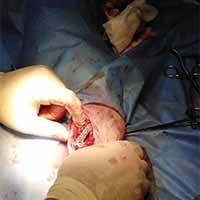

Bodrum Yalıkavak'taki kliniğimizde gerçekleştirdiğimiz yumuşak doku cerrahi uygulamaları:

Aslında bu cerrahi alan oldukça geniş bir alanı kapsamaktadır. Fakat siz yırtılan ya da kesilen deriye uygulanan cerrahi işlemler olarak düşünebilirsiniz. Daha detaylı anlatmak gerekirse; Örneğin; Erkek bir kedinin üriner taşlarından dolayı sondayla denenmesine rağmen açılmayan idrar kanalına yapılan dişileştirme operasyonu (perineal üretrostomi) da bir yumuşak doku cerrahisi operasyonudur.